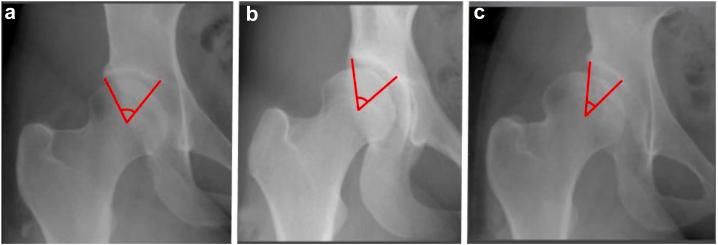

Although a variety of standardized measurements have been described to evaluate acetabular dysplasia, no single measurement is without limitations. We describe the Sourcil Index (SI), a novel measure of the weight-bearing surface of the acetabulum on anteroposterior pelvis films. The SI is the angle formed by the medial and lateral margins of the sourcil and the center of rotation of the femoral head.

尽管已经描述了多种用于评估髋臼发育不良的标准化测量方法,但没有一种测量方法是没有局限性的。我们描述了眉弓指数(SI),这是一种在骨盆前后位片上测量髋臼负重面的新方法。SI是眉弓的内侧和外侧边缘与股骨头旋转中心所形成的角度。